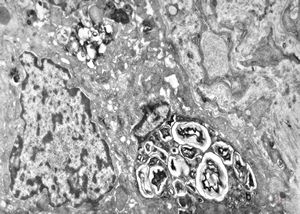

F,17y. | congenital liver fibrosis … myelinoid inclusions